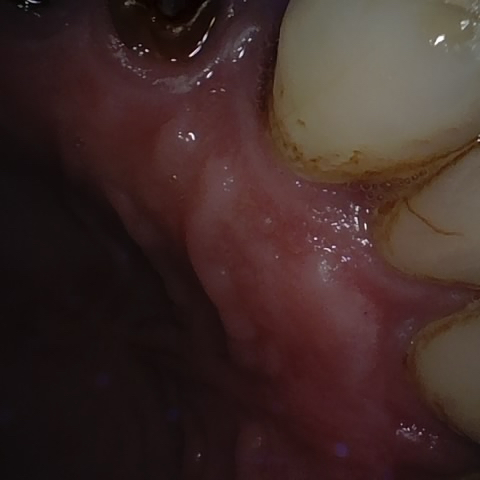

Annotated as "Good"